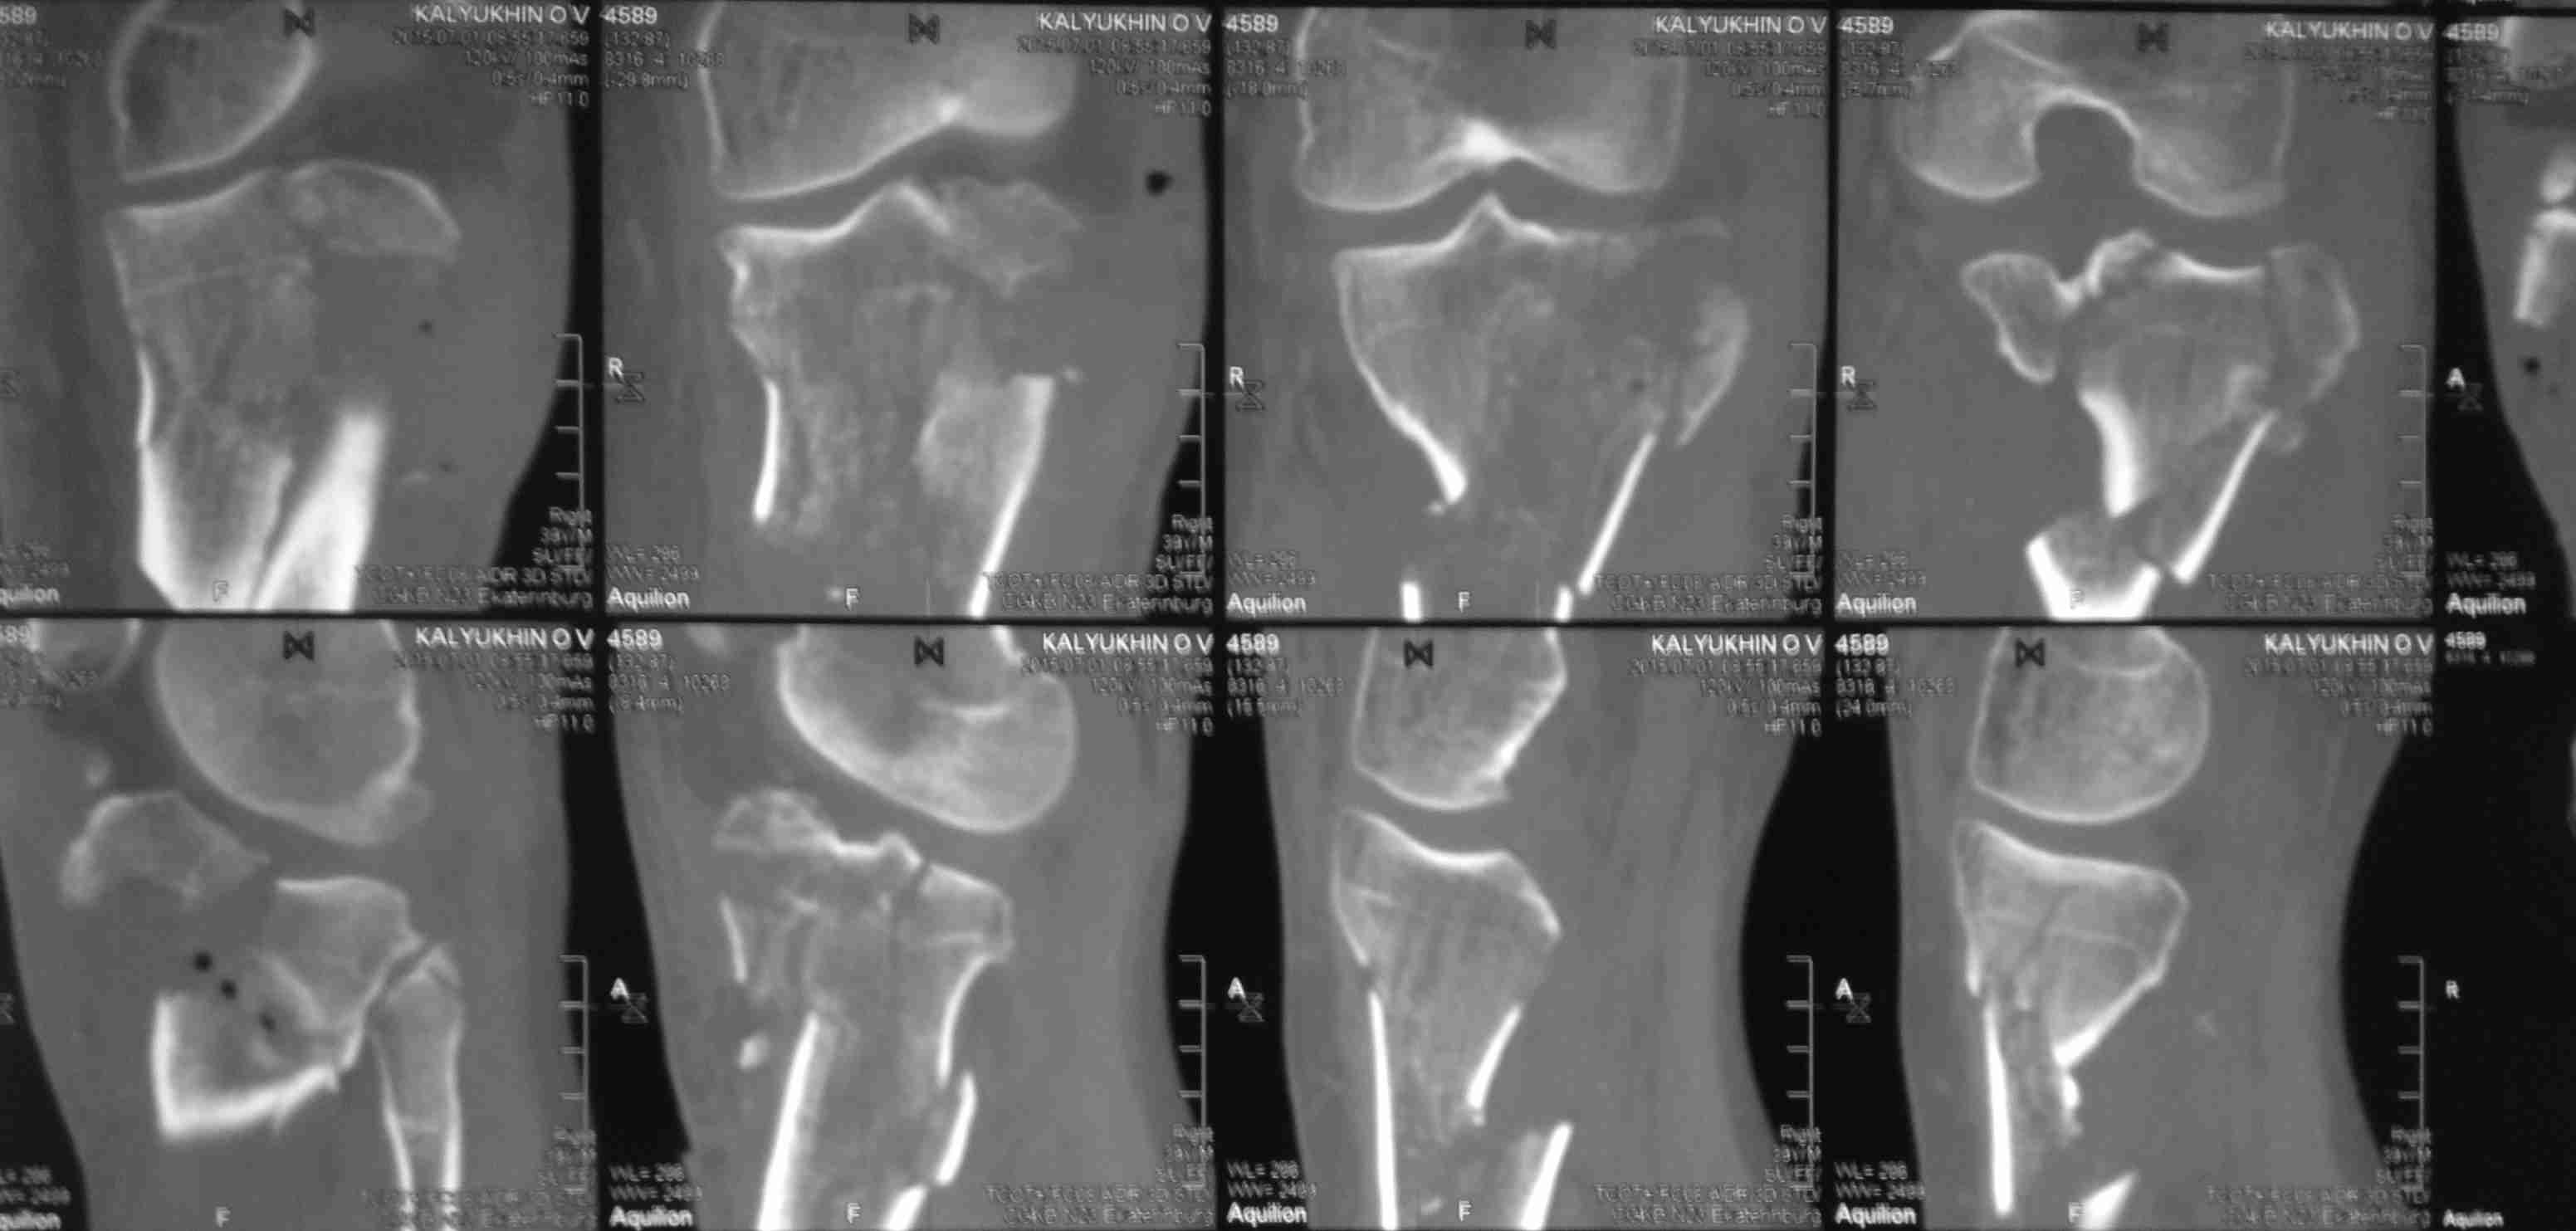

[Ortho] перелом проксимальной тибии + вывих бедра

Высокоэнергетическая травма около недели назад, мужчина 39 лет

По месту поступления вывих бедра вправлен, ПХО раны открытого перелома

б/б кости, скелетное вытяжение. В настоящее время рана заживает неплохо,

небольшое количество серозно-геморрагического отделяемого, состояние

мягких тканей неплохое. Планируем остеосинтез плато из 2-х доступов по

заживлению раны.

1 смущает фрагмент плато в проекции раны, насколько удобно его будет

ловить, попробовать полечить в аппарате + винты

закрыто?